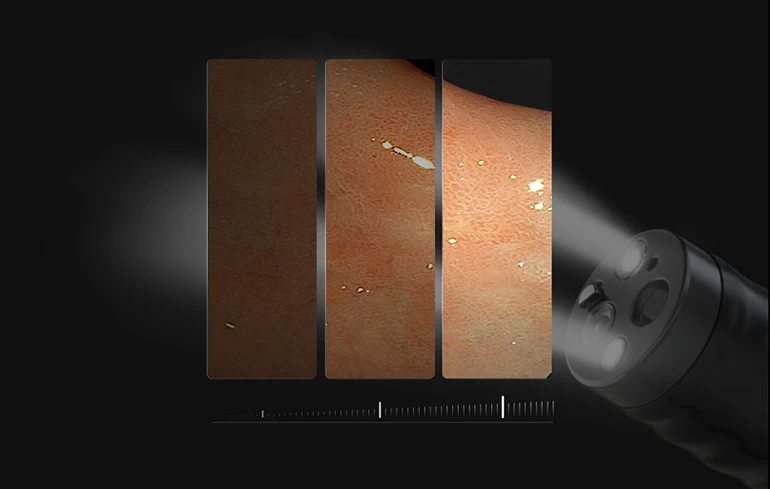

Интеллектуальное затемнение

Автоматически регулирует интенсивность освещения в зависимости от полученной интенсивности освещения. Позволяет не допустить чрезмерного освещения и эффективно контролирует температуру на дистальном конце.